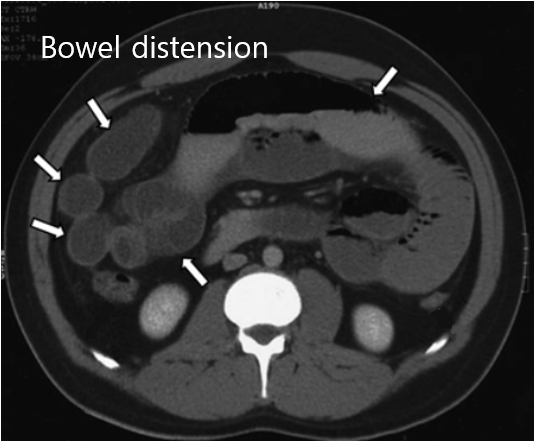

3) 진단: 복부 CT - AXR 소견에 이어 더 자세한 평가가 필요할 경우 시행

② CT: 장의 일부분이 현저히 적게 조영증강됨(= bowel ischemic necrosis)